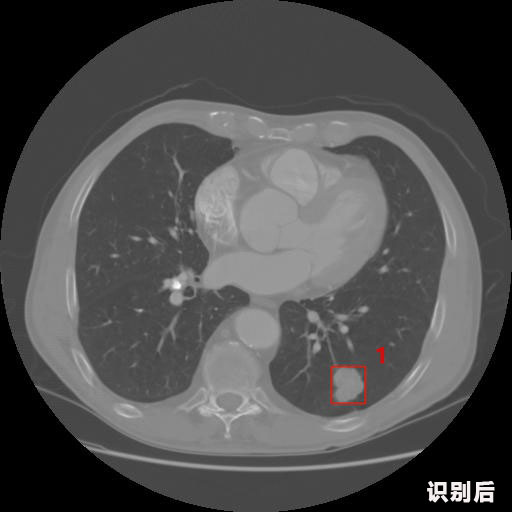

─·«ö(d©Īng)Ū░Ą─╬╗ų├Ż║ŠW(w©Żng)šŠ╩ūĒō(y©©)ą┬┬ääė(d©░ng)æB(t©żi)įö╝Ü(x©¼)┘Y┴Ž

ėó╠žĮĪ┐ĄA(ch©│)I╔ŅČ╚īW(xu©”)┴Ģ(x©¬)ßt(y©®)»¤łDŽ±ūR(sh©¬)äeŽĄĮy(t©»ng)░Ė└²_ąž▓┐CT

1.░l(f©Ī)¼F(xi©żn)Ę╬ĮY(ji©”)╣Ø(ji©”)Ą─┐╔─▄ąį×ķ95.56Żź---╬╗ė┌┐“ųĖöĄ(sh©┤)╬╗ų├Ż║[331.70554 366.13406 365.21707 403.96234]